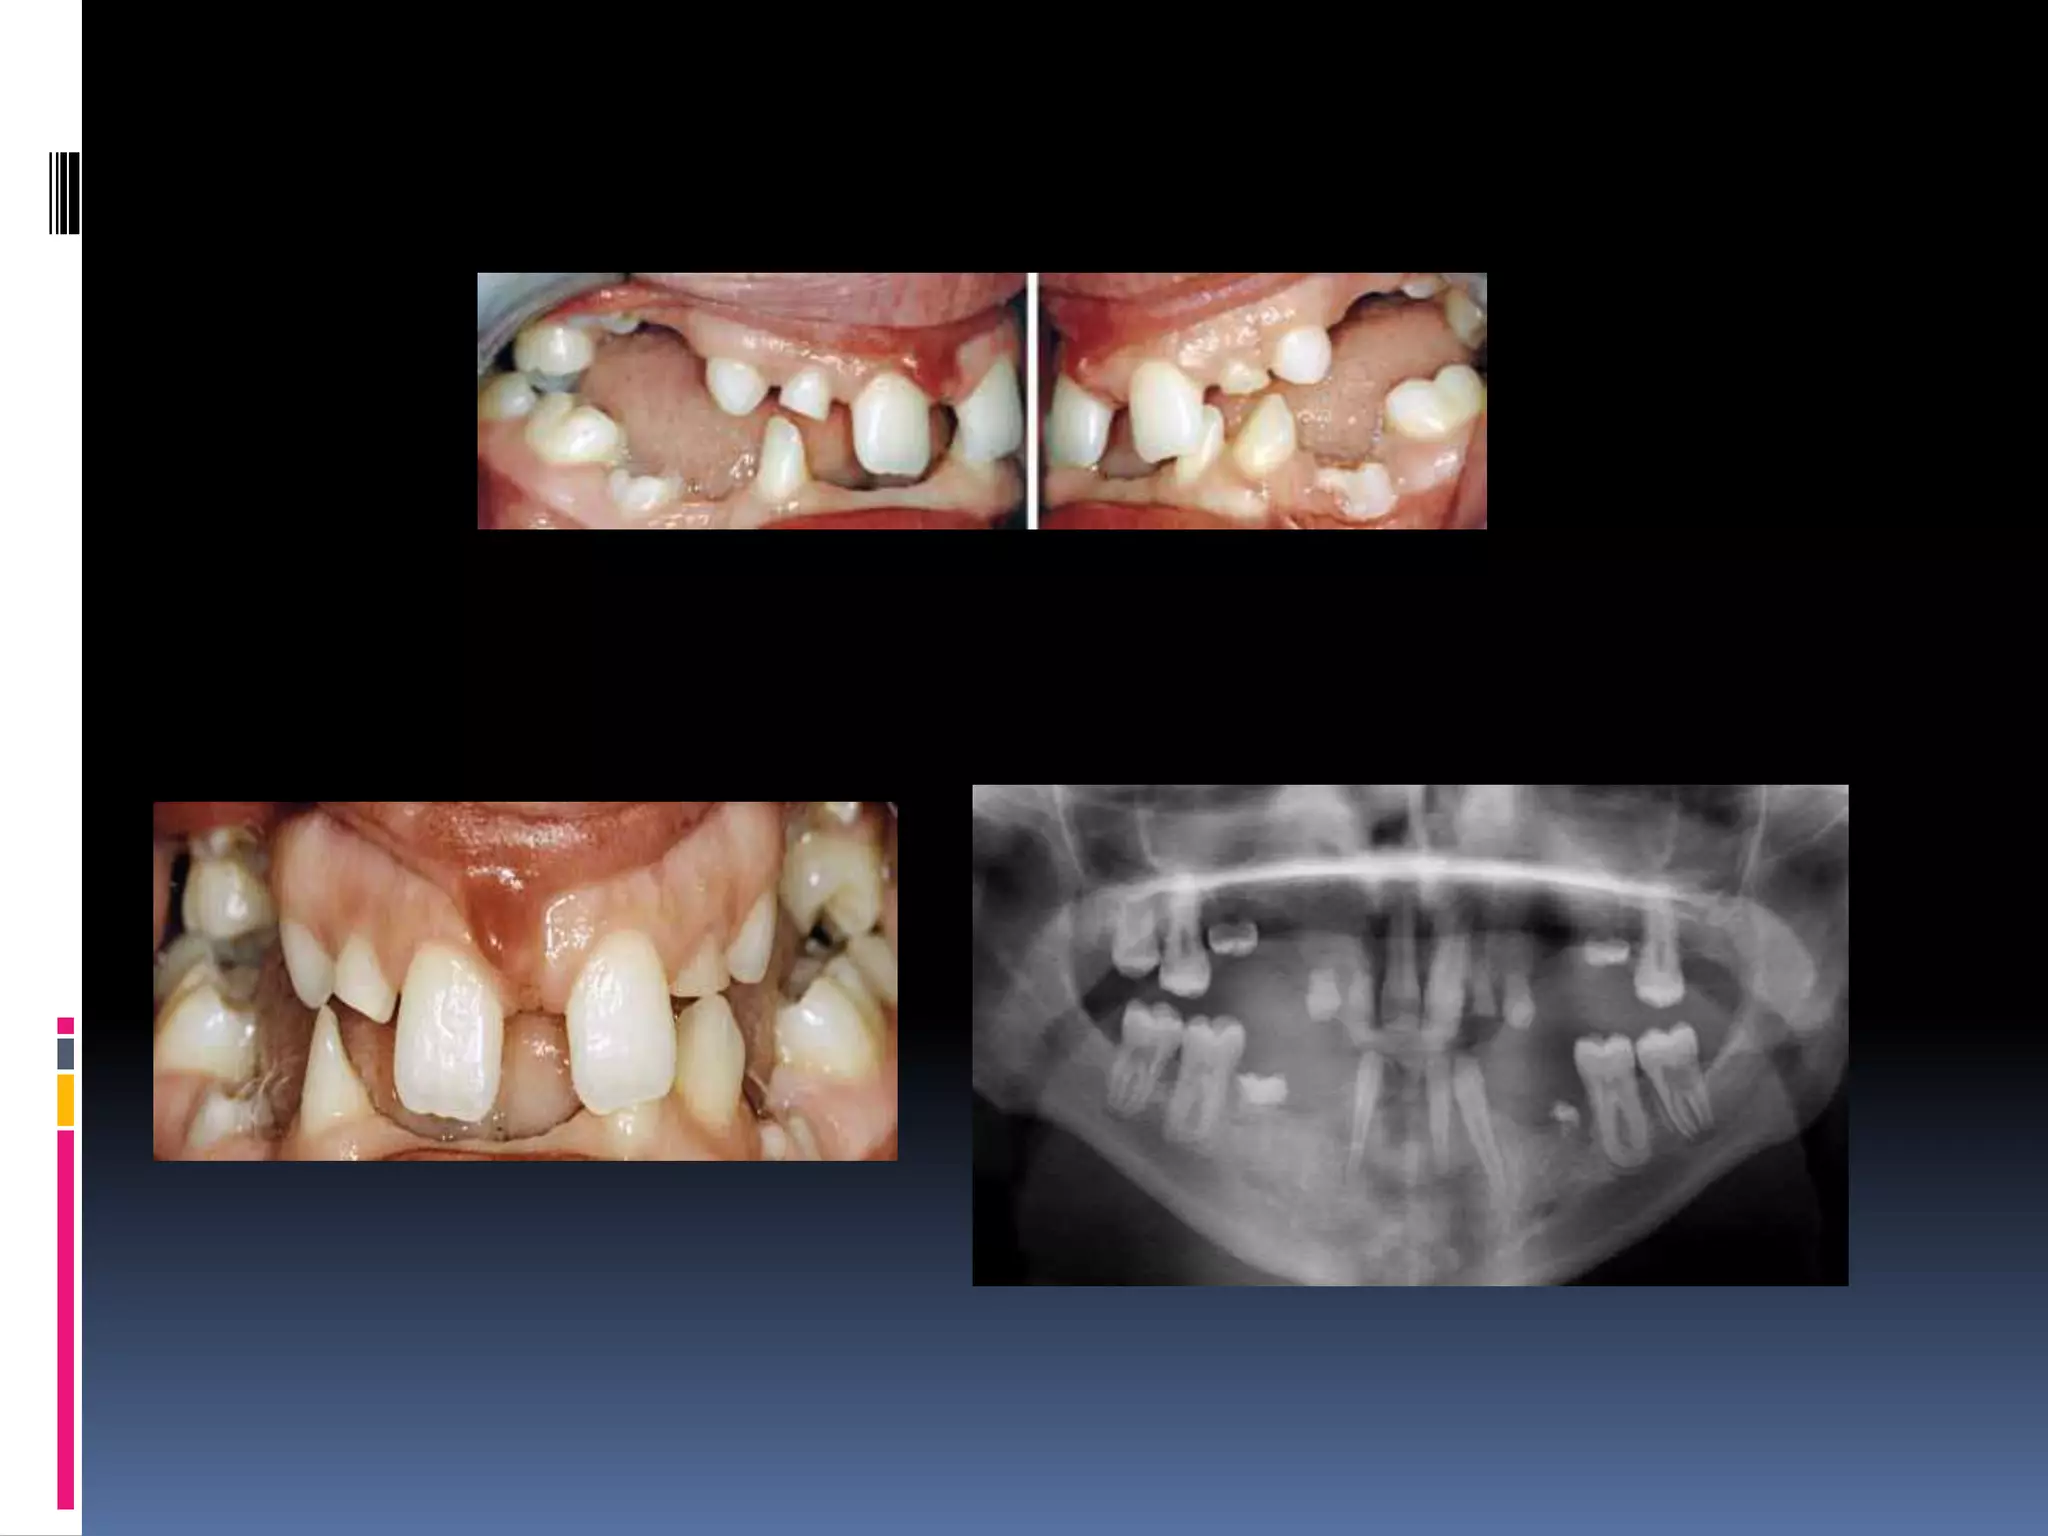

Hyperdontia

increase number of tooth

 Supernumerary- additional teeth

 Associated with macrodontia.

 Develop from third tooth bud from dental

lamina.

 Splitting of permanent bud

 Local , conditioned hyperactivity of dental

Classification of supernumerary

 According to morphology :

1)Rudimentary

abnormal shape & size.

 Conical

Peg shaped, common, as mesiodens

 Tuberculate

barrel shape anterior with> 1 cusp, less

frequent , associated with delayed incisor

eruption.

 Molariform

small molar/premolar like.

2)supplemental:

normal size & shape

common in max laterals.

 Radiology

 Panaromic radiograph with occlusal & IOPA